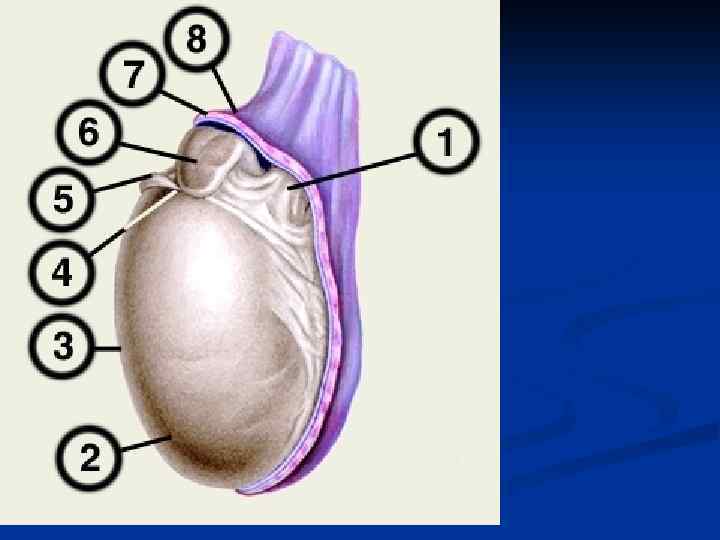

В мошонке выделяют 7 слоев (оболочек), или оболочек яичка: 1. Кожа, cutis (1) 2. Мясистая оболочка, tunica dartos (14); 3. Наружная семенная фасция, fascia spermatica externa (20); 4. Фасция мышцы, поднимающей яичко, fascia cremasterica (11); 5. Мышца, поднимающая яичко, musculus cremaster (12); 6. Внутренняя семенная фасция, fascia spermatica interna (13); 7. Влагалищная оболочка яичка, tunica vaginalis testis (18 — висцеральная пластинка; 19 — париетальная пластинка);

В мошонке выделяют 7 слоев (оболочек), или оболочек яичка: 1. Кожа, cutis (1) 2. Мясистая оболочка, tunica dartos (14); 3. Наружная семенная фасция, fascia spermatica externa (20); 4. Фасция мышцы, поднимающей яичко, fascia cremasterica (11); 5. Мышца, поднимающая яичко, musculus cremaster (12); 6. Внутренняя семенная фасция, fascia spermatica interna (13); 7. Влагалищная оболочка яичка, tunica vaginalis testis (18 — висцеральная пластинка; 19 — париетальная пластинка);